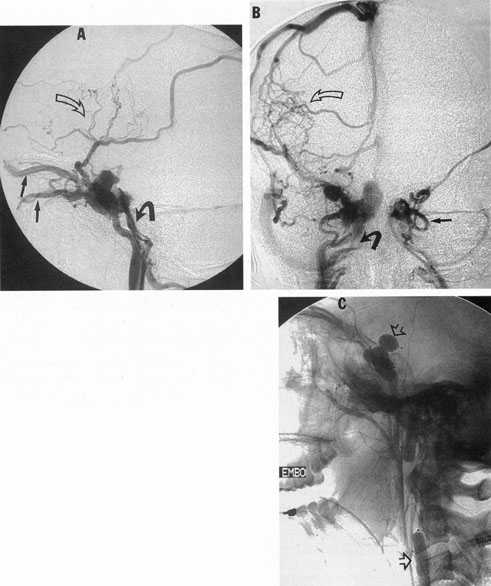

SUPRATENTORIAL

From 85% to 90% of AVMs are in the supratentorial compartment and are supplied primarily by the carotid circulation (Figs. 7 and 8). The remainder are supplied by the vertebrobasilar system. The approximate frequency of location is as follows: frontal, 22%; temporal, 18%; parietal, 27%; occipital, 5%; and deep intraventricular or paraventricular, 18%. The intracerebral site of the malformation does not necessarily indicate that there will be signs referable to that area simply from the mass effect of the malformation. Clinical features primarily result from subarachnoid hemorrhage or intraparenchymal hemorrhage with hematoma formation.

Fig. 7. Supratentorial arteriovenous malformation in a 28-year-old woman with a history of focal motor seizures for many years and a recent subarachnoid hemorrhage. A: Lateral projection carotid arteriogram demonstrating a huge deep hemispheral arteriovenous malformation. B: Frontal projection. C: Fundus photograph showing anomalous tortuous vasculature in each eye. No retinal arteriovenous shunt was detectable.

Fig. 8. Multiple supratentorial arteriovenous malformations (AVMs). A: Lateral projection of left carotid arteriogram shows dilated afferent artery (solid arrow) feeding the right hemispheric parietal AVM (open arrow). B: Right carotid injection fills a second, more posteriorly located, parietooccipital AVM (open arrow), which drains immediately to markedly dilated cortical veins (curved arrow).

In general, when hemorrhage occurs involving a portion of the visual radiations, a homonymous visual field defect is to be expected. Selective involvement of the anterior visual pathways may occur either with extensive venous angiomas at the base of the brain or as part of the Wyburn-Mason syndrome (see later), with direct involvement of the optic nerve, chiasm, or tract. Other variants such as congenital cavernous hemangiomas may involve the anterior visual pathways,68 as may intraparenchymal cryptic AVMs69 and present as symptomatic visual loss also resulting from hemorrhage and hematoma. Amaurosis fugax may even be the presenting symptom of supratentorial AVMs when blood is shunted to the meningeal circulation from the ophthalmic artery.70 When supratentorial AVMs drain into dural venous sinuses or the vein of Galen, distant ocular effects evolve, such as proptosis71 or ophthalmoplegia72 because of arterialization of cavernous sinus complex.

Of particular interest are those AVMs that involve the occipital lobe (Fig. 9). The clinical differentiation of migraine from a cerebral AVM was previously regarded as difficult because the clinical features of occipital lobe AVMs include visual phenomena or headaches. However, in most cases the clinical distinction is possible. In 26 cases with occipital AVM, two distinct syndromes were defined in 18 patients: occipital epilepsy and occipital apoplexy.73 Focal seizures with occipital malformations consist of elementary visual sensations similar to the phenomena evoked by direct cortical stimulations. When seizure activity occurs in the striate cortex (area 17), the patient usually reports sensations of moving lights in the right or left homonymous fields. The sensations are poorly formed, episodic, usually brief, sometimes colored, and unassociated with the angular, scintillating figures so characteristic of migrainous cortical phenomena. Epileptic discharges from areas 18 and 19 cause photopsias that are unlikely to remain stationary and to flicker rapidly. The epileptic photopsias usually last only seconds; occasionally they last for a few minutes before the onset of a generalized seizure. In other instances only the brief visual episodes occur without spreading to produce a generalized seizure. Momentary dimming or blindness in one or both homonymous fields may be experienced with seizure activity in the occipital areas.

Fig. 9. Carotid arteriogram of an occipital lobe arteriovenous malformation (AVM). Lateral (A) and frontal (B) projections demonstrating a small occipital AVM (arrow). The patient was a 23-year-old woman who presented with severe apoplectic unilateral headache, total left homonymous hemianopia, and mild nuchal rigidity. Despite xanthochromic cerebrospinal fluid, she was initially diagnosed elsewhere as having migraine. An AVM was successfully resected, and a small occipital lobe hematoma was removed.